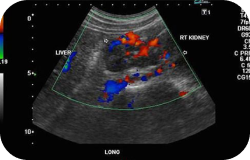

A safe and painless ultrasound is performed to produce a picture of the organs and other structures in the upper abdomen, including the liver, gallbladder, spleen, pancreas, and kidneys. This test is used to find the cause of abdominal pain; check the size, shape, and position of the liver; detect gallstones, inflammation of the gallbladder, or blocked bile ducts; learn the size of an enlarged spleen and look for damage or disease; find problems with the pancreas; find out the size of the kidneys, detect kidney masses, detect fluid surrounding the kidneys, investigate causes for recurring urinary tract infections, or check the condition of transplanted kidneys; and find out whether a mass in any of the abdominal organs is a solid tumor or a simple fluid-filled cyst.